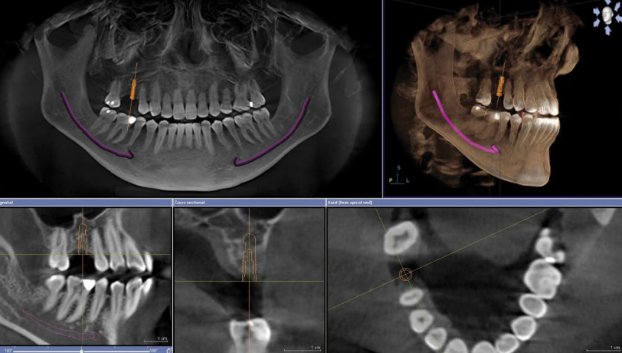

- CBCT (Cone Beam Computed Tomography): Provides 3D visualization of bone volume, density, and vital anatomical structures

The foundation of accurate surgical guide fabrication lies in proper data acquisition:

- CBCT scan specifications:

- Minimum resolution: 0.3mm voxel size for clear visualization of bone details

- Full arch scans are recommended for comprehensive planning

- Precise registration of CBCT and intraoral scan data

- Verification of alignment accuracy through anatomical landmarks

- Software-based correction of minor discrepancies

- High-resolution CBCT (0.25mm voxel size) captured bone anatomy

- Intraoral scanning documented existing dentition and soft tissue contours